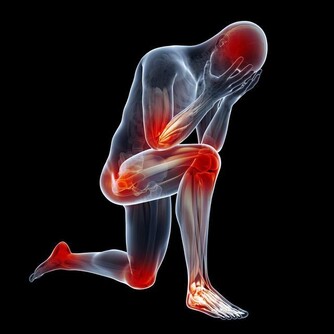

為了時尚、個性,有的女人一年四季都穿裙裝,膝蓋和關節暴露在外,難免遭受風、寒、濕等外邪的侵擾,引起關節疼痛。

很多這樣的女性,她們歲數都不大,但早早就有了腿痛的毛病。

關節部位受寒疼痛,可不是一天兩天形成的,正所謂,冰凍三尺非一日之寒。

在這裡,提醒各位愛穿裙裝的姐妹,無論有沒有關節疼痛,都要重視關節的保養。